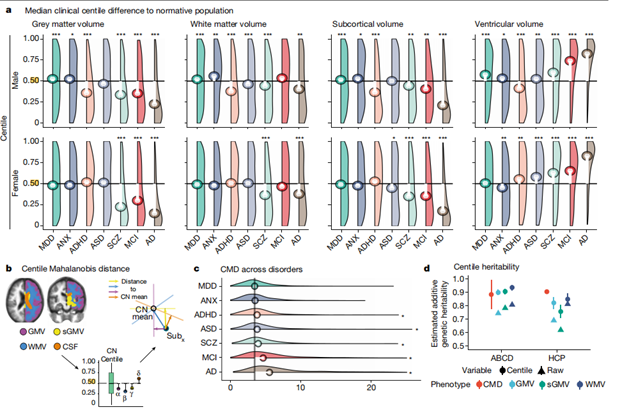

利用与年龄相关的标准化脑图进行了基准测试,计算了个体化百分位分数。汇总数据集的临床多样性,使研究能够全面分析百分位数得分的病例-对照差异。相对于对照组(CN),在诊断为多种疾病的大(N>500)病例组中,百分位数得分存在显著差异(图4)。临床病例对照分析中,皮质厚度和表面积的差异,与体积组间差异的趋势类似。阿尔茨海默病的总体差异最大,女性患者中灰质体积差异最大(中位数百分位数评分=14%,与CN中位数相差36个百分点,图4a)。此外,本文引入了一个累积偏差度量,即百分位数马氏距离(CMD)。精神分裂症的CMD在总体上排名第三,仅次于阿尔茨海默病和轻度认知障碍(MCI)(图4c)。

在生命周期的所有主要时期中,无论诊断类别如何,病例中的CMD始终高于对照组。不同时期最大的病例对照差异发生在成年晚期和青春期。成年晚期罹患痴呆的风险增加。在青春期,精神健康障碍发病率增大。

图4.:百分位数的病例-对照组得分的差异和遗传力。